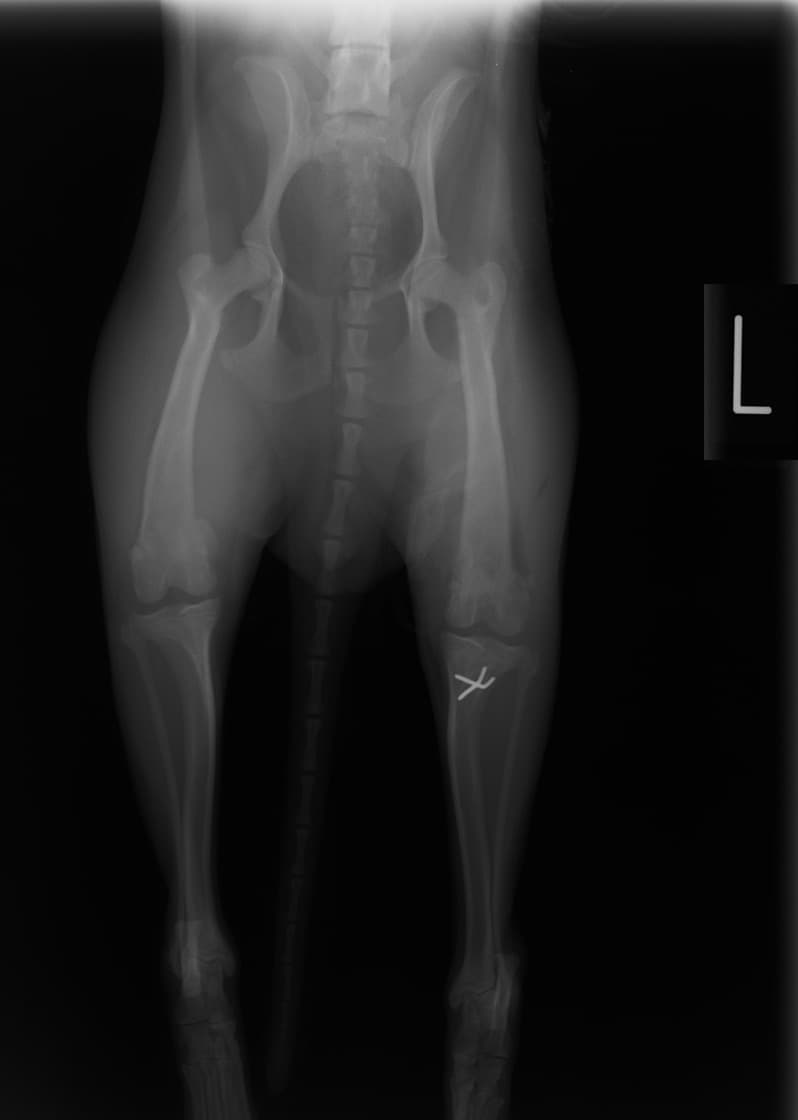

■ 症例24 キャバリア 7か月

左右膝蓋骨内方脱臼(左:グレードⅣ 右:グレードⅢ)

以前から左右後肢の跛行が認められ、整形外科学的検査・レントゲン検査により左右の膝蓋骨脱臼が認められた。症状が重度である左膝の膝蓋骨脱臼整復術を行った。外科手技は縫工筋及び内側広筋の解放、脛骨粗面の外側転位、滑車ブロック形造溝術、内外側関節方の縫縮を実施した。術後一か月時点で、左の膝蓋骨は安定しており経過は良好である。

本症例は成長期における重度の膝蓋骨脱臼であり、術後の再発の可能性もあるため、経過をしっかりと観察していく必要がある。また、今回手術を実施していない右膝に関しても経過を観察し、手術を検討していくこととする。